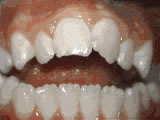

Open bite - Front teeth don't touch

Patient sucked her thumb as a young child. She started treatment at age 13. She had braces and a special appliance — called a crib — to retrain the tongue, for 28 months. Now she can bite the lettuce out of a sandwich.